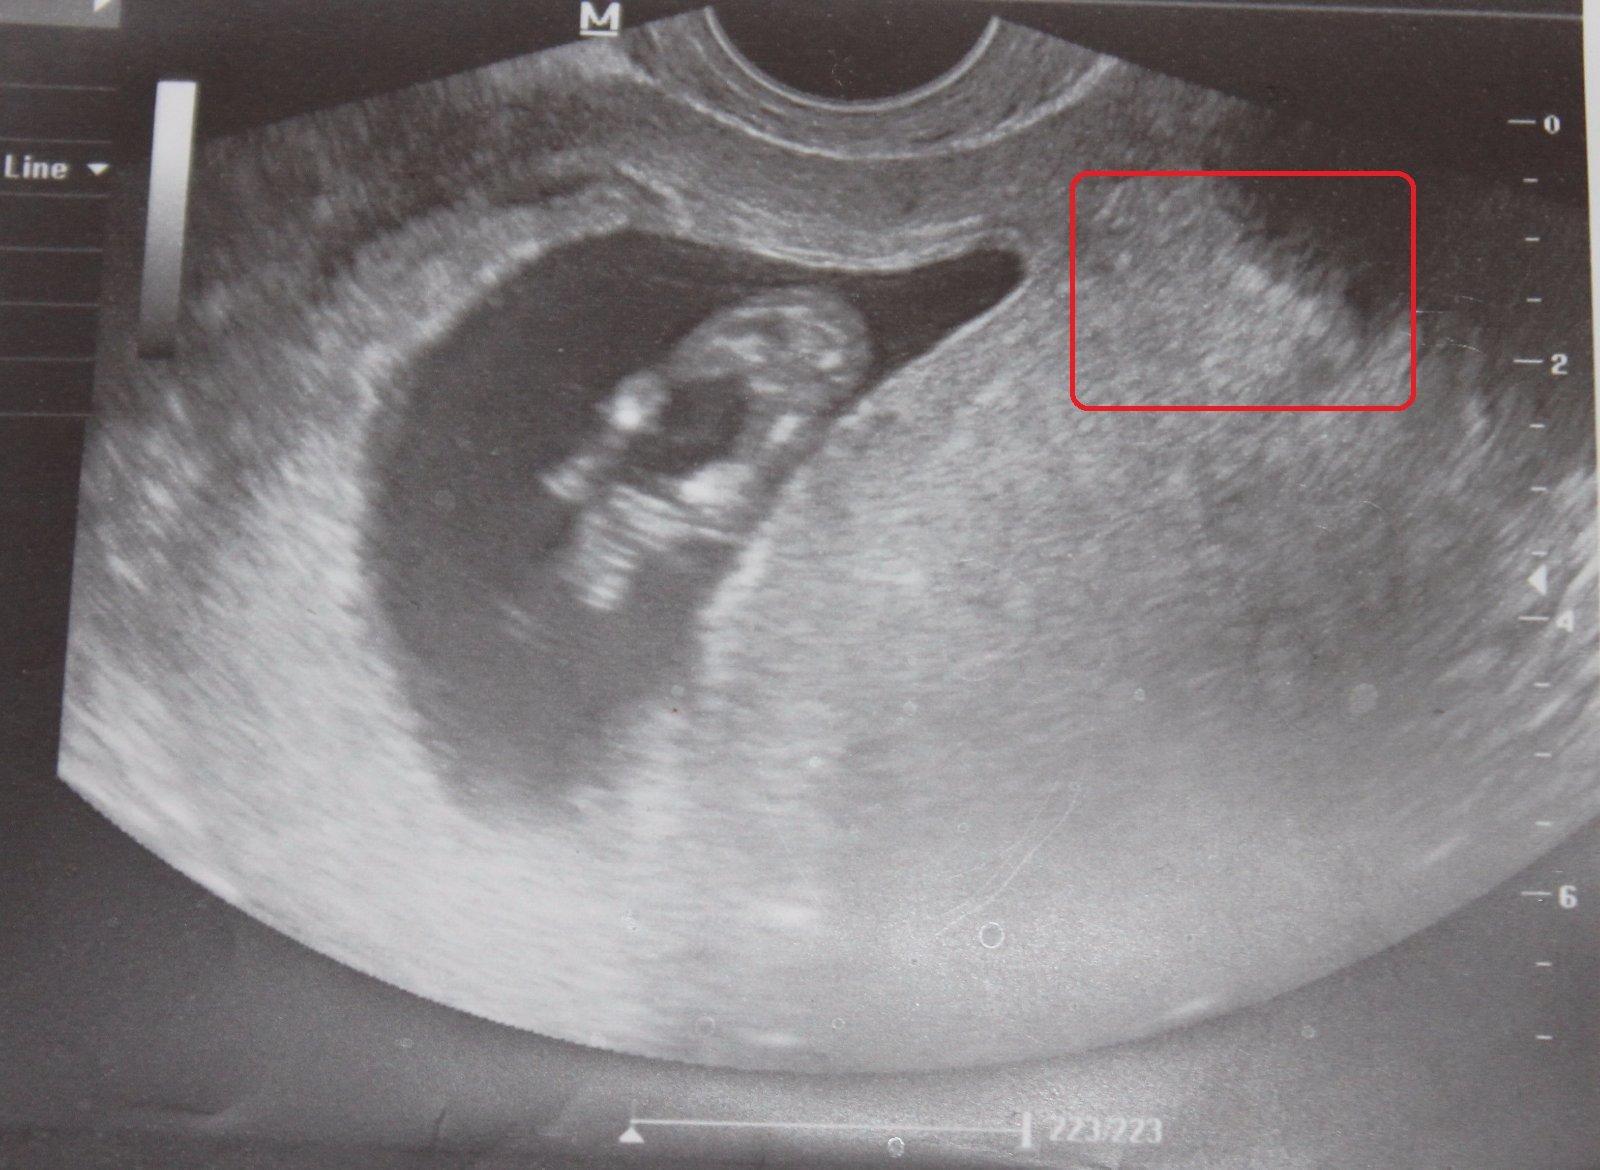

Ahojte maminy a cakatelky, prosim vas pekne, zda sa to iba mne alebo vidite na obrazku z UZ viac ako jedno babatko? dve fotky vytvorene tesne po sebe a na prvej vidim vpravo v hornom rohu (akoby za ciernou dutinou) babatko spredu (hlavicka a lava rucicka) a hned na druhej zozadu akoby stavce, hlavicku a svetle "ciarky" - nozicky. Totiz cim viac to pozorujem, tym viac neviem na com som. Podla mna sa pocas "fotenia" otocilo lebo aj to prve sa velmi rychlo stale hybalo. Prosim vidi este niekto okrem mna viac ako jedno dietatko ci nie? dakujem za vase nazory, DAKUJEM velmi velmi!

PS to dietatko ( aj ked vidno iba jeho cast) v strede v tej tmavociernej casti je iste a potvrdene doktorom... ;)

@amanra neviem, tak videla som vela uzv fotiek dvojiciek, a vyzeralo to celkom inak... ten vak malo kazde babo svoj vacok,a bolo to pekne vidiet....proste tak zretelne,ako toto prve babo,tak bolo vidno aj druhe, popripade bolo jedno vidiet dobre, a druhe len rucku,nozicky,ale tie vaky bolo vidiet normalne.... Toto sive vzadu,nevyzera velmi ako vak, skor ako tien, alebo mocovy mechur... alebo neviem, vajecnik...nieco take, nie babetko 🙂 Ale nie som lekar,cize pisem len to co vidim, a vidim len jedno babo 🙂 Vsak uvidime,pojde pani/slecna na uzv o 2 tyzdne ,a napise nam 🙂

@stratenanajdena Jaj, tak a preco ti nepustil zvuk srdiecka? 🙂 Mne ked robil vaginalny uzv, tak mi pustal stale srdiecko, a stale bilo len jedno 🙂 🙂 Vsak uvidis,ked ti pusti zvuk, ked budu bit dve srdiecka budes mat istotu ze tam su dvaja, ale podla tych fotiek to vyzera na jedno, inak by druhe bolo bez vaku,ale uvidis.